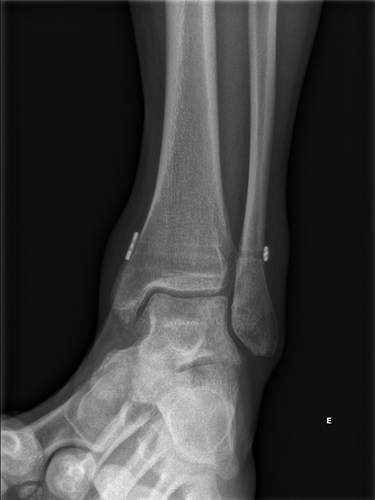

Geralmente a suspeita diagnóstica é confirmada com exames de imagem. A radiografa em carga pode logo ser confirmatória em lesões grosseiras. Em lesões mais subtis, é necessário a realização de ressonância magnética.

• Lesão de Grau III (Grave): Rotura completa dos ligamentos da sindesmose com diástase clara entre a tíbia e a fíbula (já visível no Rx), resultando em instabilidade evidente do tornozelo.

Em lesões instáveis, grau IIB (com instabilidade ao exame objetivo) e III o tratamento é cirúrgico, consistindo numa artroscopia do tornozelo, com redução e estabilização da sindesmose, mantendo a tíbia e o peróneo unidos durante a cicatrização dos ligamentos. Em casos onde há rotura extensas ou crónicas, pode ser necessário reconstruir os ligamentos usando enxertos ou outras técnicas cirúrgicas.